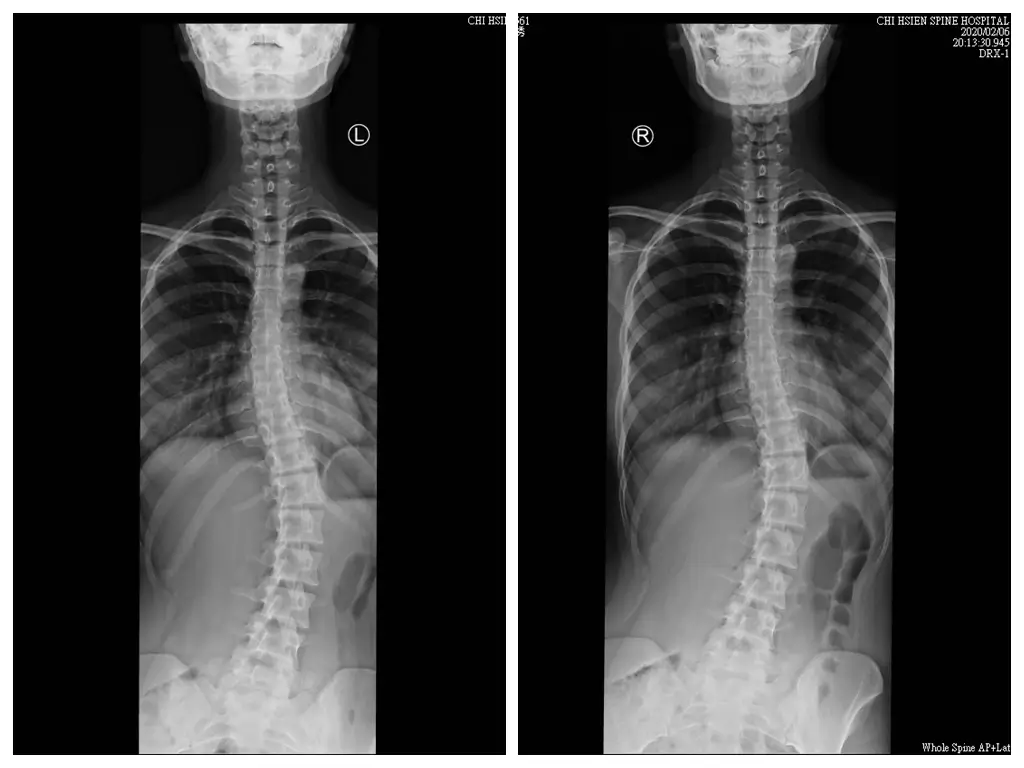

目前我對於脊椎側彎的理解、是可以分成先天性與後天性成因,先天性的成因一般的認知都是未明、

而後天性的則多是姿勢不良所造成的,所以我們對於這兩種成因的調整觀點也不同;

先天性的脊椎側彎隨者每個案例的發展不同,我認為可以介入的時間點也不同,一般而言可以區分成發育期以前與發育期以後作為分界,如果是發育期以前發現,我認為的黃金治療期是在13-18歲、也就是國中高中這六年,這時我們的骨骼開始快速發展,這個時候介入可以對發展角度作最大程度的影響,但若在此之前即發現有脊椎側彎,除非角度有快速惡化、否則都視情況作症狀調整,等候進入黃金治療期時再密集調整;

發育期以後的脊椎側彎,由於骨骼已經發育完全,這時候的調整目標則是以消除其不良症狀、維持生活品質;